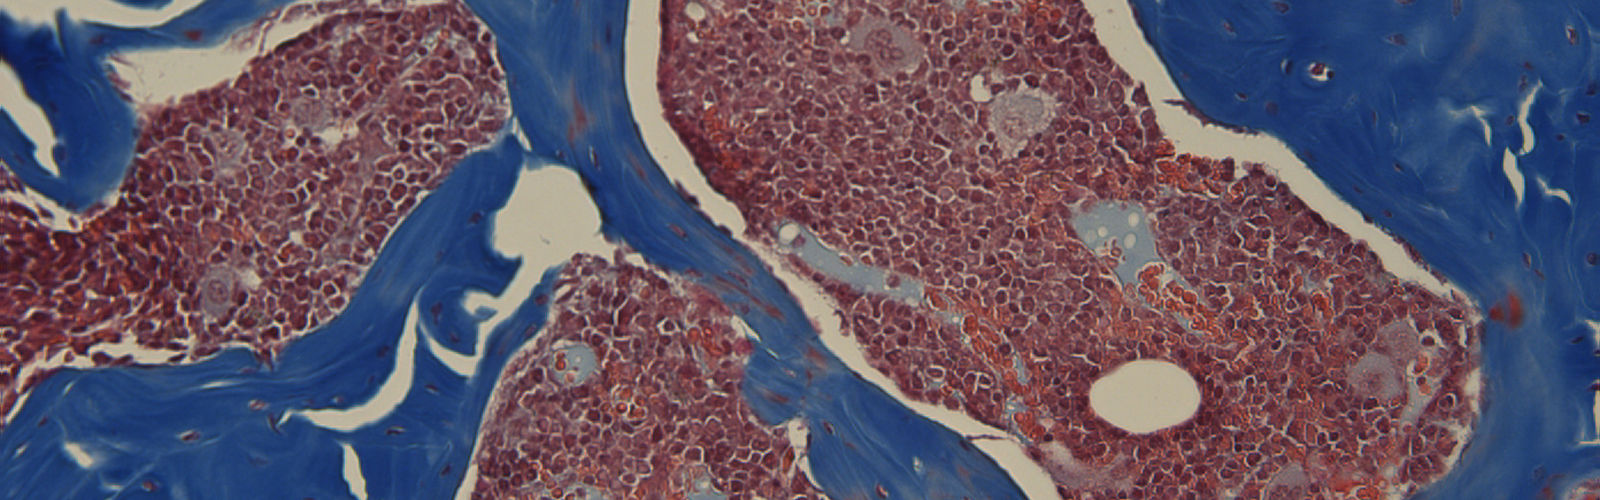

• Platelets and MKs During Infection

• Megakaryocyte-mediated platelet changes During Infection